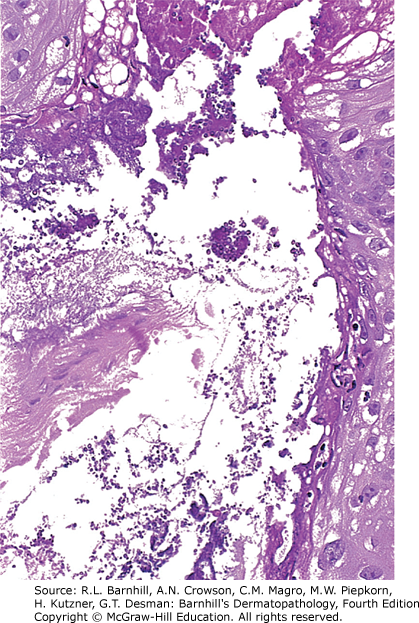

B. Bacterial folliculitis typically shows a dense perifollicular neutrophilic infiltrate and gram-positive organisms both of which can be seen in the image below.